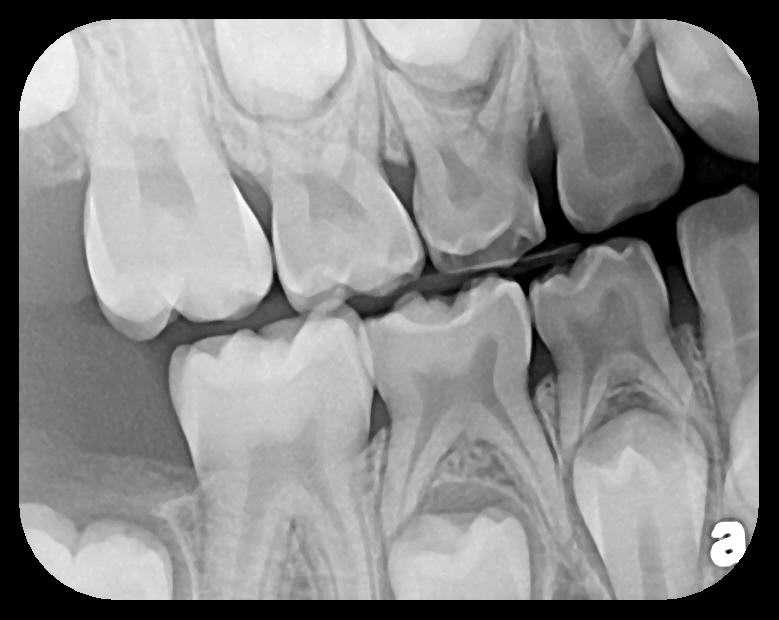

There are two specific types of DIDR sensor systems available to dentists in the marketplace: the hard-wired (HW) sensor and the photostimulable phosphor (PSP) sensor,1,2 also commonly known as phosphor "plates." A desirable feature common to both modalities is the ability to expose either bitewing (BW) or PA radiographic images. The BW radiograph (Figure 1) is usually considered more appropriate for caries detection, whereas the PA (Figure 2) is diagnostic for several different anatomic and pathologic issues.7

Fig 2. Left: PSP vertical PA radiograph of

maxillary bicuspid area demonstrating full root structure, several millimeters of bony anatomy beyond apices and maxillary sinus. Tooth No. 4 may be

traumatized as periodontal ligament is widened. Right: PSP horizontal PA radiograph of maxillary bicuspid area. Tooth No. 12 shows widened apical

periodontal ligament presumably caused by deep restorative filling. Some loss of supporting bone is evident interproximally, especially pronounced

between tooth Nos. 14 and 15.

Figure 2